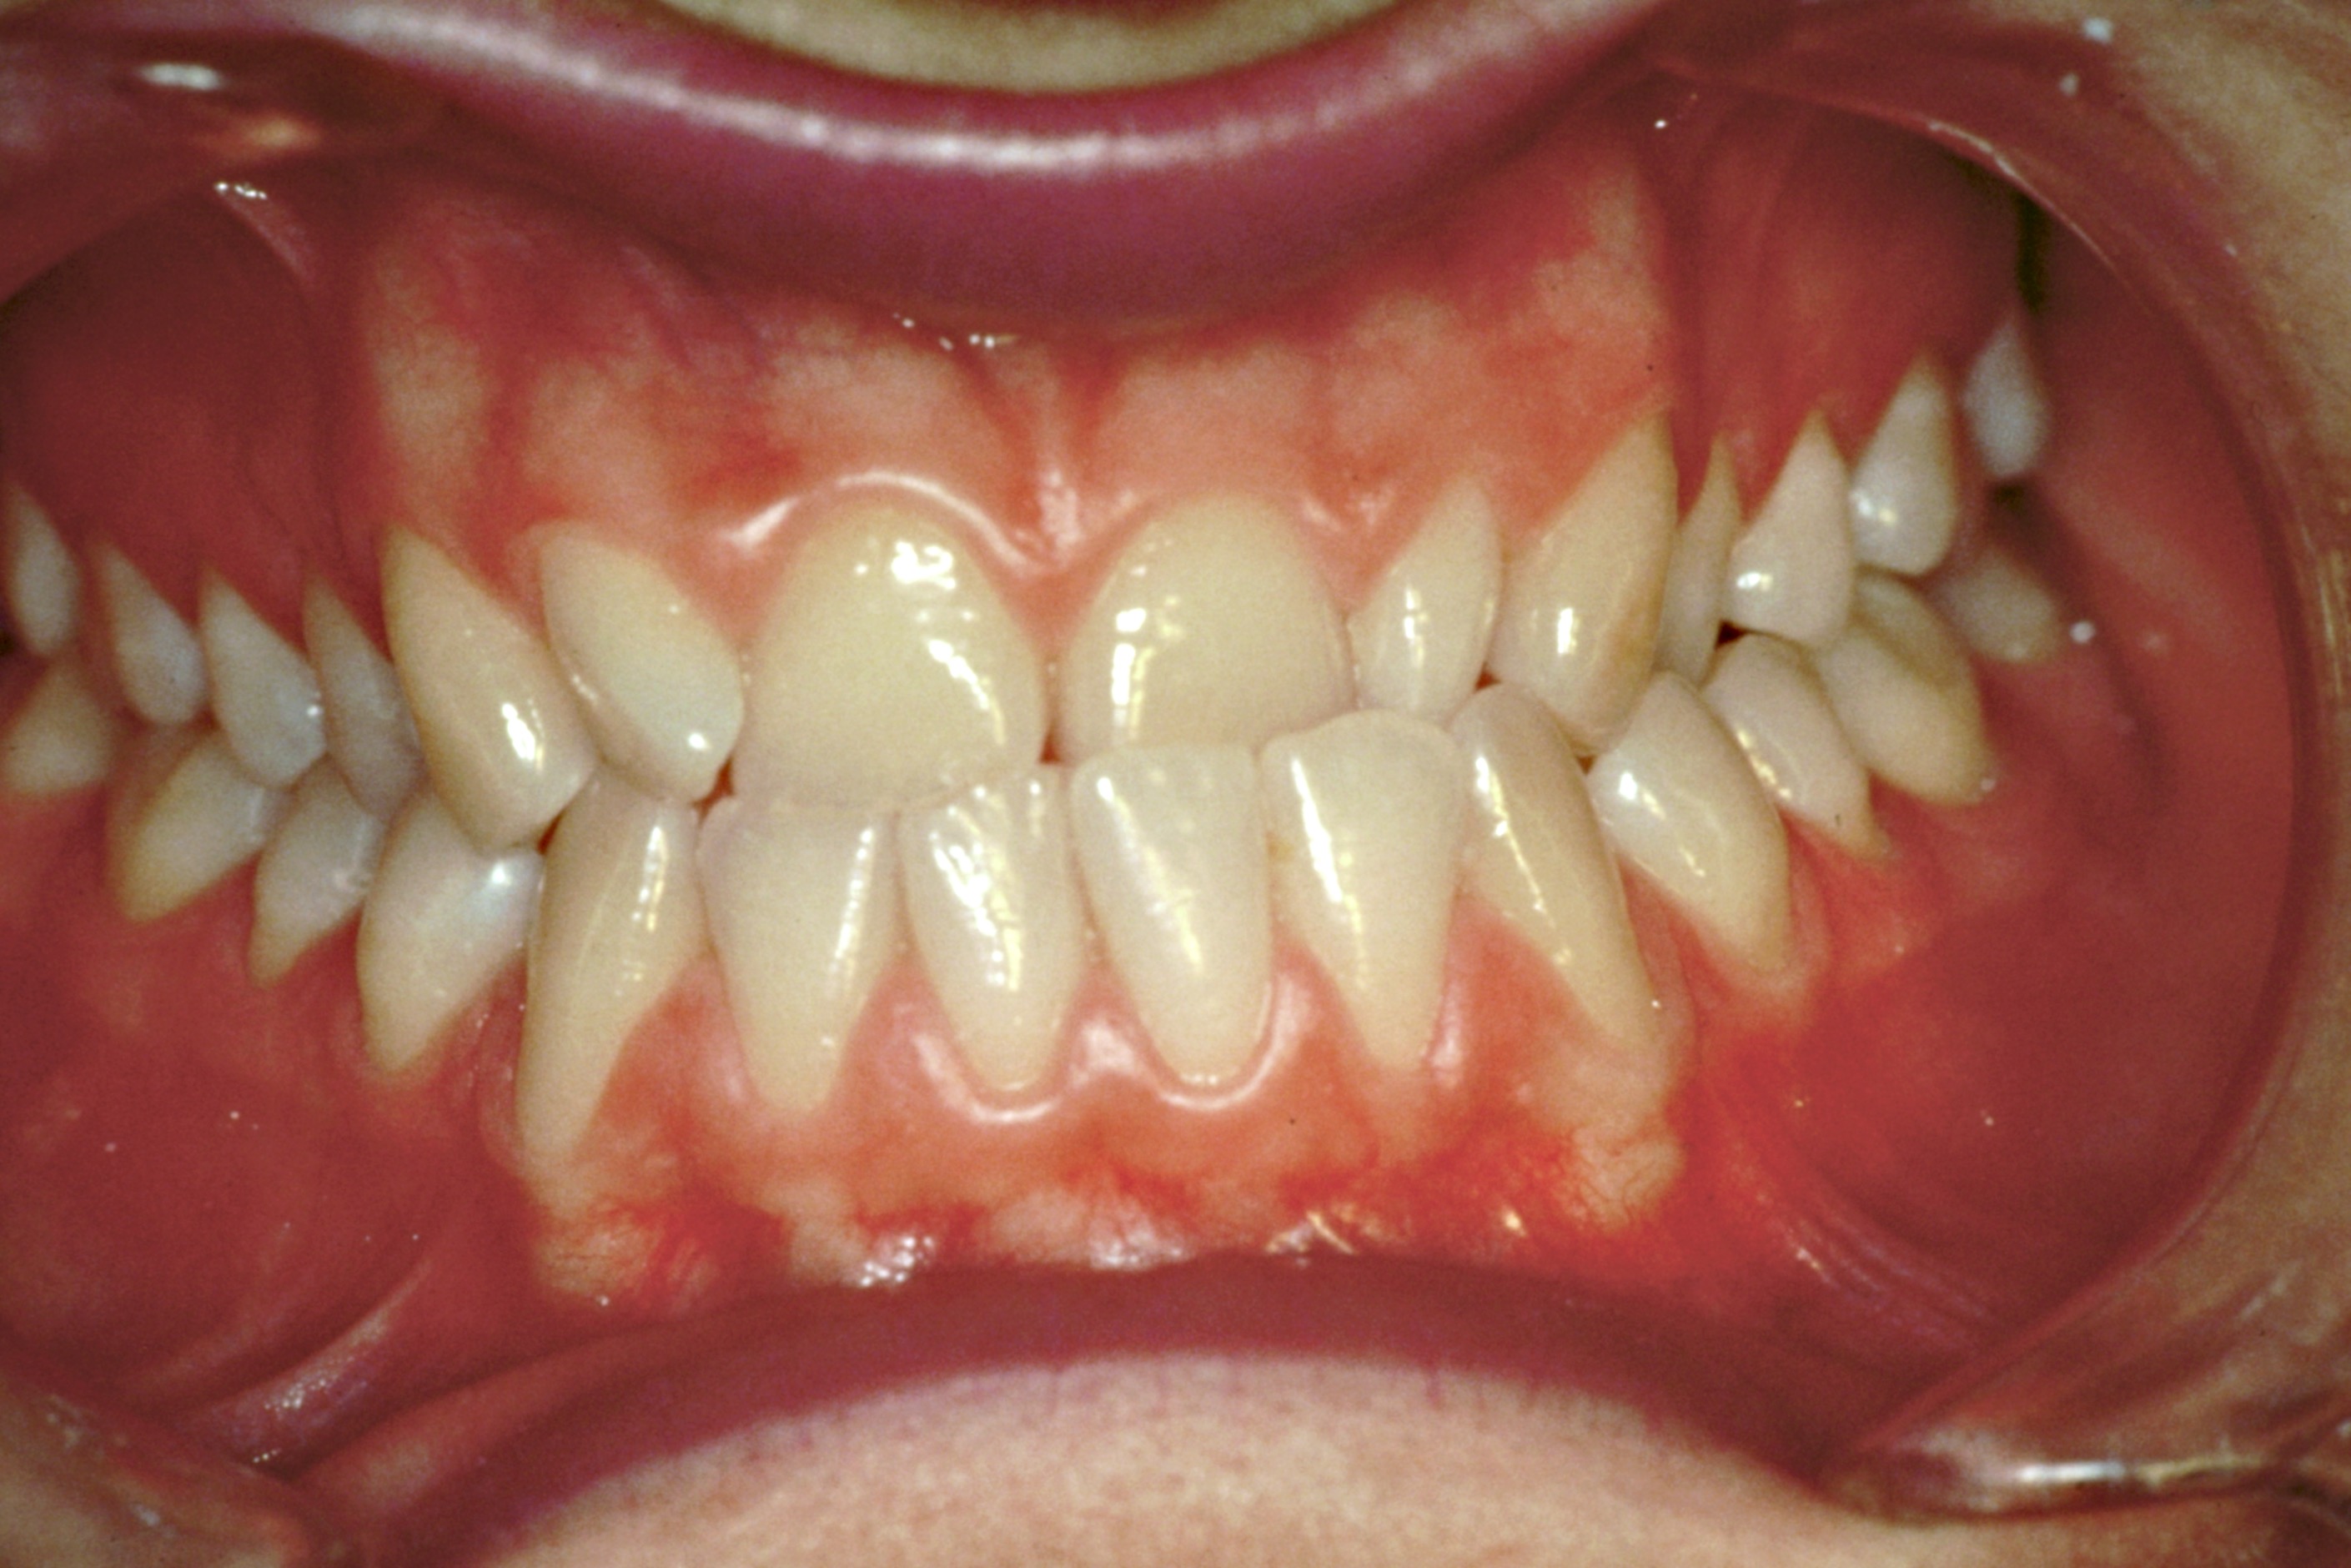

Scénarios diagnostiques récurrents observés au sein du Masticationpedia Network (et non des rapports de cas isolés). Tous les centres du Network habilités utilisent des technologies et des méthodologies neurophysiologiques permettant des diagnostics précoces et précis de pathologies imitant des symptomatologies odontologiques, telles que les Troubles Temporo-Mandibulaires et les Douleurs Orofaciales, qui peuvent parfois masquer des atteintes organiques neurologiques et systémiques. En outre, le savoir-faire acquis permet un contrôle et une finalisation des traitements orthodontiques, prothétiques et implantoprothétiques optimisés selon les réponses neurophysiologiques trigéminales, et non uniquement sur des paramètres de forme et d’esthétique.

Traitements orthodontiques fixes

Orthodontie fixe

Neuro-ortho-gnathodontie

Orthodontie interceptive

Neuro-orthodontie interceptive